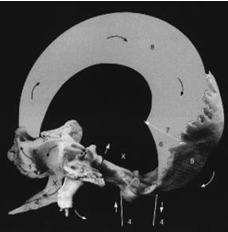

Рис. 59. Фиброзные мембраны человеческого организма

Рис. 61. Участие внутричерепных мембран в дыхательном ритме [252]

Рис. 62. Висцеральные связи грудной полости и гортанно-глоточно-язычная ветвь внутреннего хода